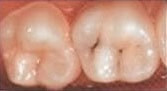

Eine Fissurenversiegelung der Zähne ist eine wirksame Methode, um Zähne vor Karies zu schützen. Dabei sind manche Zähne anfälliger als andere. Backenzähne sind insbesondere aufgrund ihrer großen Kaufläche und Position anfälliger von Karies angegriffen zu werden als Schneidezähne. Denn auch die Reinigung der Zahnoberfläche wie der Außenwände ist durch die Stellung meist komplizierter.

Zunächst einmal werden die Zähne auf ihren Zustand geprüft. Denn nur gesunde Zähne werden versiegelt. Anschließend werden die Zähne gereinigt. Dabei wird hartnäckiger Zahnbelag bzw. Zahnstein abgetragen. Sind die Zähne von Plaque befreit, werden sie getrocknet, damit der Kunststoff besser haften kann. Um die Zähne leicht anzurauen, verwendet nun der Zahnarzt eine spezielle Säure. Zum Schluss werden die Kauflächen, Rillen und Furchen der Zähne mit einer dünnen Schicht aus Kunststoff oder Glasionomerzement überzogen und mit einer speziellen Lampe ausgehärtet. Dadurch werden die für Karies besonders anfälligen Fissuren verschlossen.